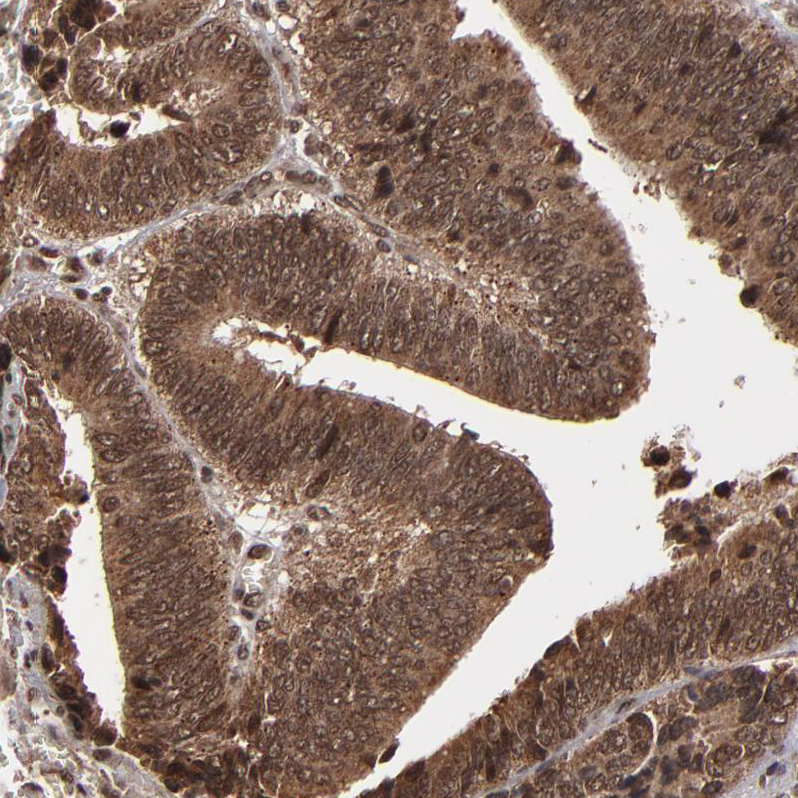

Immunohistochemical staining of human testis shows strong nuclear positivity in cells in seminiferous ducts.